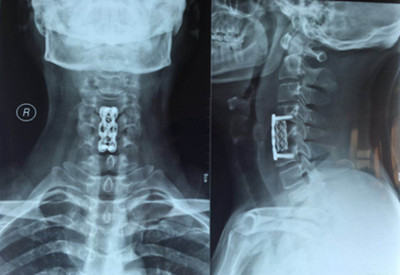

近日,骨一科成功實(shí)施一例高難度頸椎手術(shù)——頸椎前路頸5椎體次全切、椎管減壓植骨融合內(nèi)固定術(shù)。

患者王先生,34歲,兩個月來自覺行走時雙下肢無力,伴踩棉花感,休息后癥狀無明顯緩解,雙手指麻木,呈加重趨勢。一月前就診于骨一科。確診為頸椎病(脊髓型)。病變部位位于頸5-6平面。

因患者年齡較輕,雙下肢無力癥狀明顯,病變區(qū)脊髓信號改變,保守治療病情會繼續(xù)發(fā)展,后期脊髓神經(jīng)變性,壓迫癥狀加重,嚴(yán)重影響肢體功能,必須盡早手術(shù)。骨一科主任楊志奎帶領(lǐng)曹熙、田濤、張凱迪醫(yī)師為其實(shí)施了頸椎前路頸5椎體次全切、椎管減壓植骨融合內(nèi)固定術(shù)。手術(shù)歷時3小時順利完成。術(shù)后第二天,患者雙手指麻木癥狀明顯緩解,四肢關(guān)節(jié)活動均正常。第三天配帶頸托保護(hù)下床活動鍛煉,雙下肢無力癥狀明顯減輕。患者現(xiàn)已康復(fù)出院。

4月23日王先生來院復(fù)查:雙手指麻木感、雙下肢無力感消失,四肢肌肉力量恢復(fù),行走姿態(tài)正常,病情恢復(fù)理想。